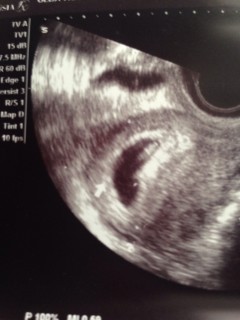

6週~7週目と言われました‼︎ピコピコ動いている心拍も確認できました。赤ちゃんの大きさ2.5と大きめ?腹痛が少しありますがひとまず安心しています。

赤ちゃんの大きさは7.9ミリで心拍も確認できました♪ 先生にも順調です。って言ってもらえて安心しました。